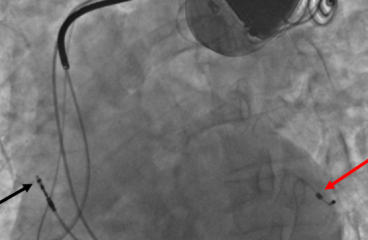

CRTD therapy for heart failure is best done at Agra Heart Centre by Dr Rajat Rawat and Dr CR Rawat. This is the only and best hospital offering CRTD therapy in Agra